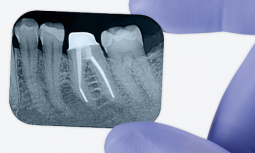

Post and core procedures – or root canals, as they are more commonly known – are very

complex restorations. That’s why we engineered the 3M Post and Core Solution for synergy and simplicity: these products work together to help you make a long story short. With fewer clinical steps, the 3M Post and Core Solution makes the endodontic restorative procedure simpler for both you and your patient, without sacrificing reliability. So you can get the job done faster. All with just four products.

Based on over 700 post placements, 92% of dentists responded they were satisfied or very satisfied with the overall performance of the system. In particular, the new RelyX™ Fiber Post 3D Glass Fiber Post was rated excellent for its easy handling, good esthetics and significantly improved radiopacity. Combined with our clinically proven cement and simple bulk restorative, that translates to a convenient, fast and reliable procedure – time after time.